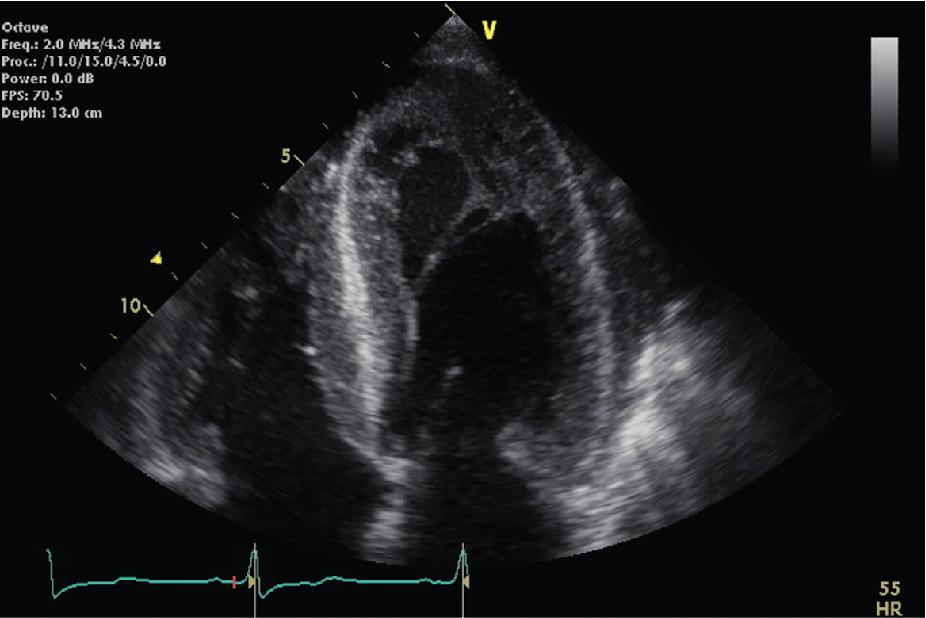

• Patients with severe AS unlikely to benefit from TAVI include patients with cardiac amyloidosis characterized on TTE by increased LV wall thickness ( Figs. 4.5 and 4.6 ), abnormal tissue Doppler measurements, LV strain ( Fig. 4.7 ) and a characteristic “speckled” pattern as the amyloid protein is more echogenic than standard myocardium (see Figs. 4.5 and 4.6 ).

Fig. 4.5, Increased LV wall thickness and a characteristic “speckled” pattern in diastole in an 83-year-old with severe AS and confirmed cardiac amyloidosis. AS , Aortic stenosis; LV , left ventricular.

Fig. 4.6, Increased LV wall thickness and a characteristic “speckled” pattern in systole with cavity obliteration.